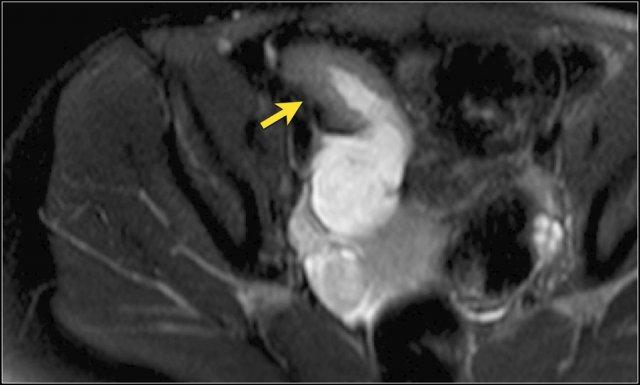

Hình ảnh T1W sau tiêm thuốc tương phản mặt phẳng coronal cho thấy hẹp tại vùng nối hồi manh tràng (trái). Không thấy giãn ruột trước chỗ hẹp rõ ràng. Chỗ hẹp không thể vượt qua được khi nội soi (phải).

Hẹp lòng ruột

Hẹp lòng ruột có thể biểu hiện bằng hình ảnh thành ruột dày kết hợp với lòng ruột bị thu hẹp.

Sự hiện diện của giãn ruột trước chỗ hẹp làm tăng khả năng chẩn đoán hẹp lòng ruột.

Ngấm thuốc tương phản bất thường của đoạn ruột bị ảnh hưởng thường hiện diện.

Trong hệ thống phân độ, chỉ hẹp nặng mới được xếp vào nhóm biến chứng, được định nghĩa là hẹp có giãn ruột trước chỗ hẹp và tín hiệu T2W thành ruột tăng mức độ vừa đến rõ rệt.

Hình ảnh thu hẹp lòng ruột có thể do co thắt gây ra, vì vậy cần kiểm tra các chuỗi xung khác trước khi đưa ra chẩn đoán hẹp lòng ruột.

Chuỗi xung đánh giá nhu động ruột có thể có vai trò trong việc xác định sự hiện diện hay vắng mặt của nhu động, nhằm phân biệt co thắt với hẹp thực sự.